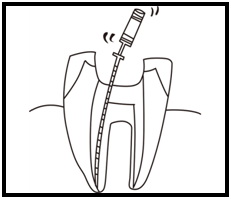

⑤ 次に、仮詰めをします。

⑤ 次に、仮詰めをします。 虫歯が神経まで達して炎症を起こしているので、人によってはズキズキとした痛みを感じる方もいます(>_<)